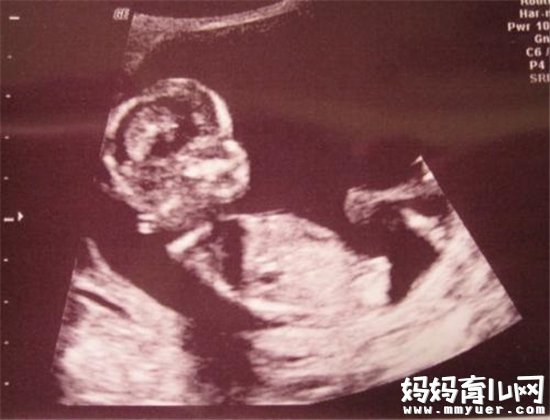

的确是,虽然是男是女都喜欢,不过好奇心驱使还是让很多关心孕妈妈的人们其实包括孕妈妈都想提前知道。既然国家规定不能提前泄露,但我们可以在B超单上看出些蛛丝马迹来,那么B超怎么看胎儿性别呢?下面跟随小编一起来看看吧~

B超怎么看胎儿性别之看形状

妈妈们可以在怀孕两个月的时候去做B超,如果宝宝的形状是长型的,像茄子或长条状的,那么很有可能是男宝宝,若是椭圆或是圆型,那么可能是女宝宝。

如果妈妈是孕晚期,也可以看B超图,对着你的,一般是女宝宝,背着的,一般是男宝宝。